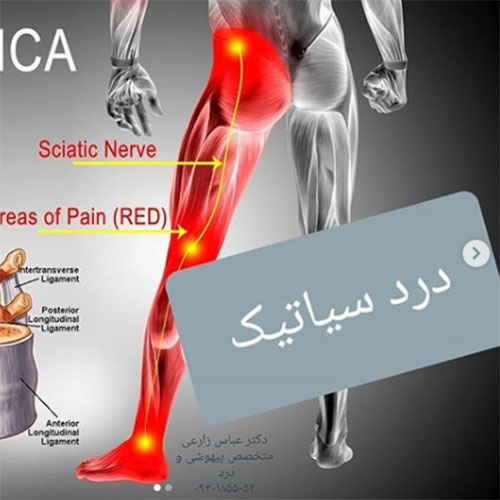

بیماری دیسک کمر

دیسک کمر دلیل شایع بسیاری از دردهای حاد، مزمن و دردهای عود کننده ی کمر و پا می باشد. معمولا بیشترین آسیب ها در دیسکهای L4-L5 یا L5-S1 ایجاد می شود ولی گاهی ممکن است در دیسک های بالاتر کمری نیز مشکل وجود داشته باشد. درد ممکن است در پائین کمر، باسن، لگن و پاها احساس شود.

علائم: پارگی دیسک کمر ممکن است بدون علامت بوده و یا با علائم زیر همراه باشد:

درد پشت، شکل غیر طبیعی ستون مهره ها، محدودیت حرکتی در ستون فقرات بخصوص خم شدن، نقص نورولوژیک در منطقه ی خاصی از اندامها، دردهای ناشی از آسیب عصبی، کاهش حس پوستی در اندام ها، کاهش یا فقدان رفلکس های تاندونی در اندام ها، گاهی اوقات ضعف و/یا تحلیل عضلانی.

علائم فوق معمولا یکطرفه اند ولی زمانی که دیسک دچار آسیب شدیدی در بخش مرکزی باشد و ریشه های عصبی دو طرف تحت تاثیر قرار گرفته باشند علائم بالینی دوطرفه دیده می شود.